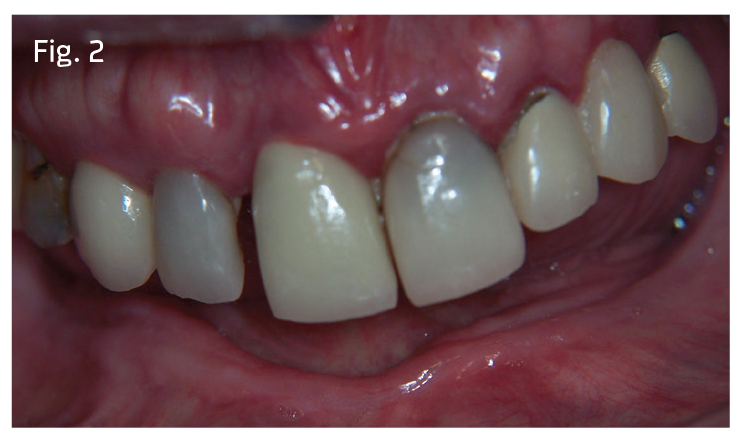

Visit #1: We gathered all diagnostic data—full-mouth radiographs (Fig. 1), preop photos (Fig. 2), CBCT scan (Fig. 3) and study model impressions. The patient was mildly sedated—30 milligrams of hydroxyzine slurry swallowed and 0.125mg triazolam crushed sublingually—and monitored with pulse oximeter throughout the treatment phase of the appointment.